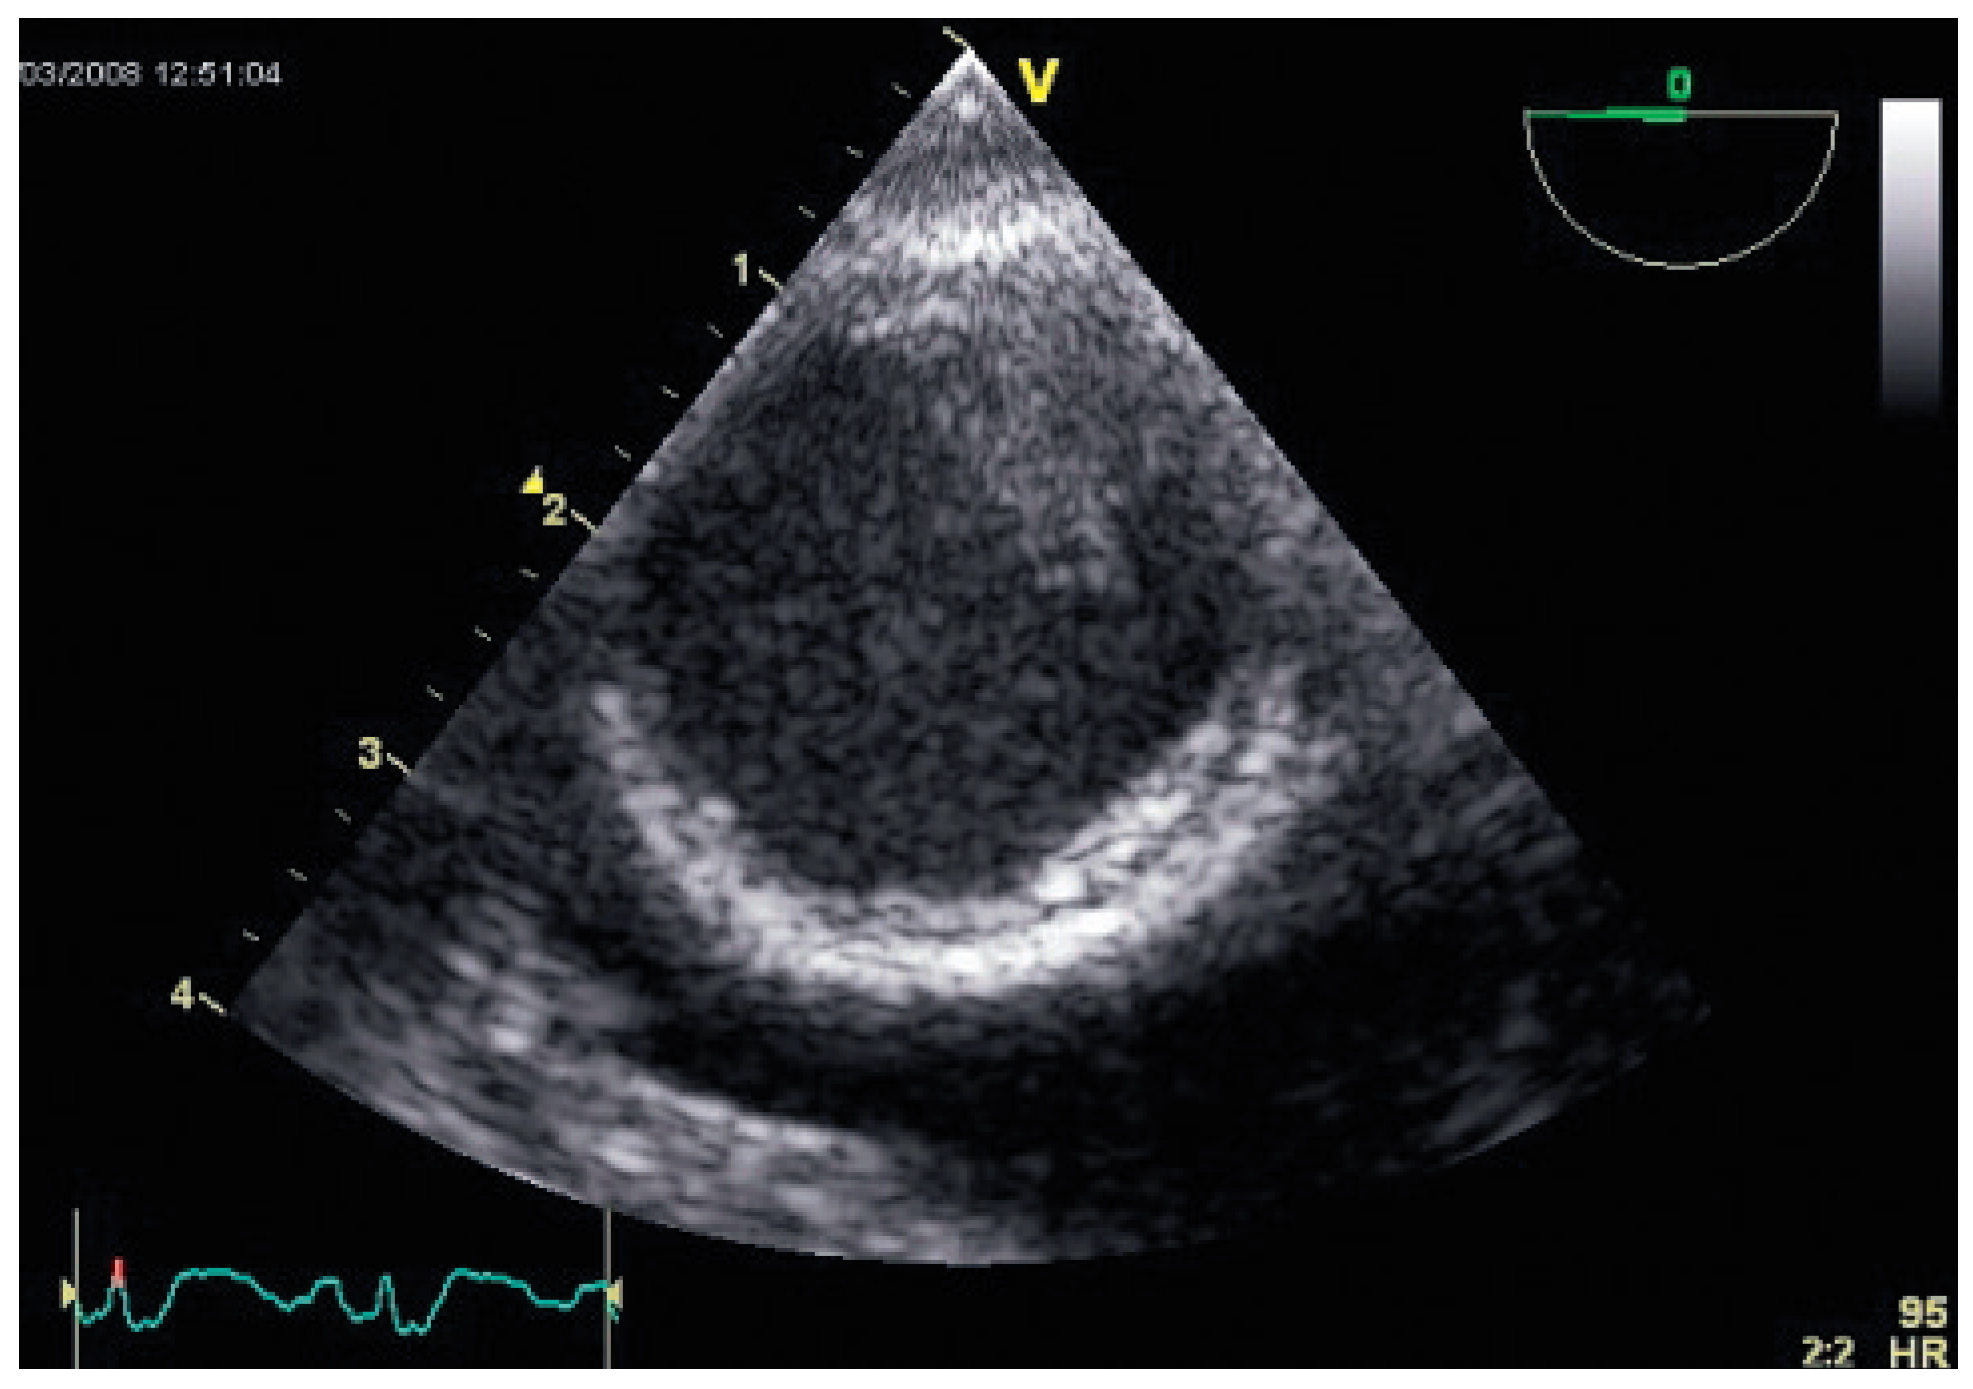

Flottierender Thrombus in der Aorta Descendens